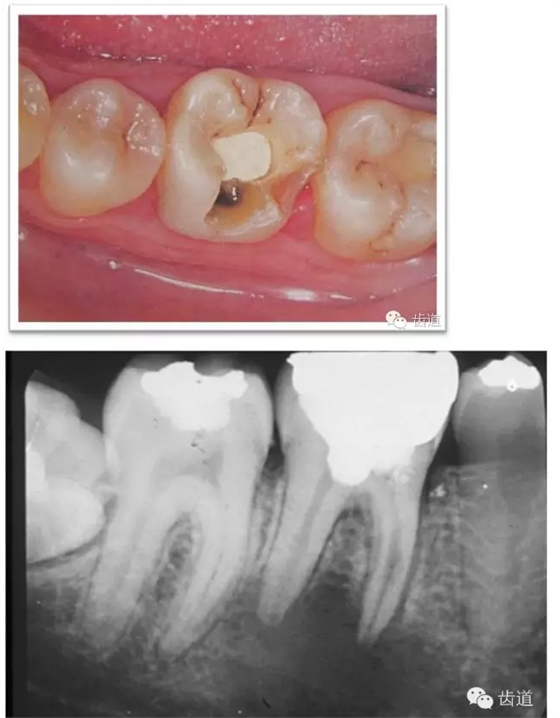

l實(shí)際備牙產(chǎn)生的問(wèn)題

l防止過(guò)度預(yù)備(造成牙髓激惹)

l保留活髓(保留牙體的整體性和韌性)

l過(guò)度預(yù)備抗力形喪失